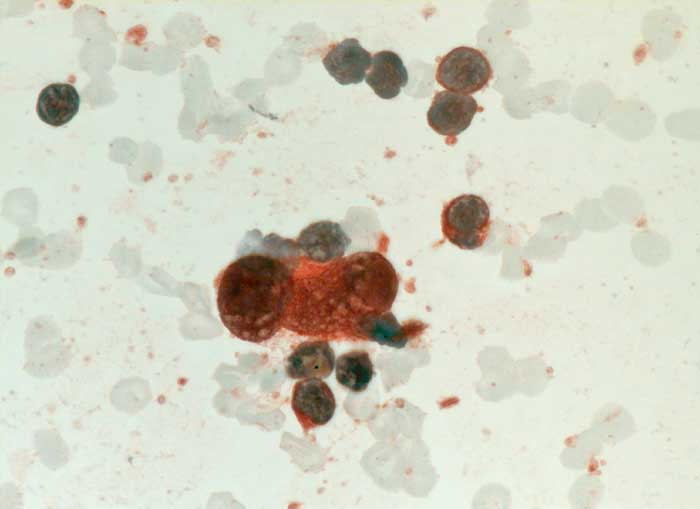

Reed-Sternberg Zellen und Hodgkin Zellen des klassischen Hodgkin Lymphoms (lymphozytenreich, noduläre Sklerose, Mischzelltyp, lymphozytenarm) sind positiv für CD15 und CD30. Die Tumorzellen des nodulären lymphozytenprädominanten Subtyps hingegen sind positiv für CD20 und CD45.